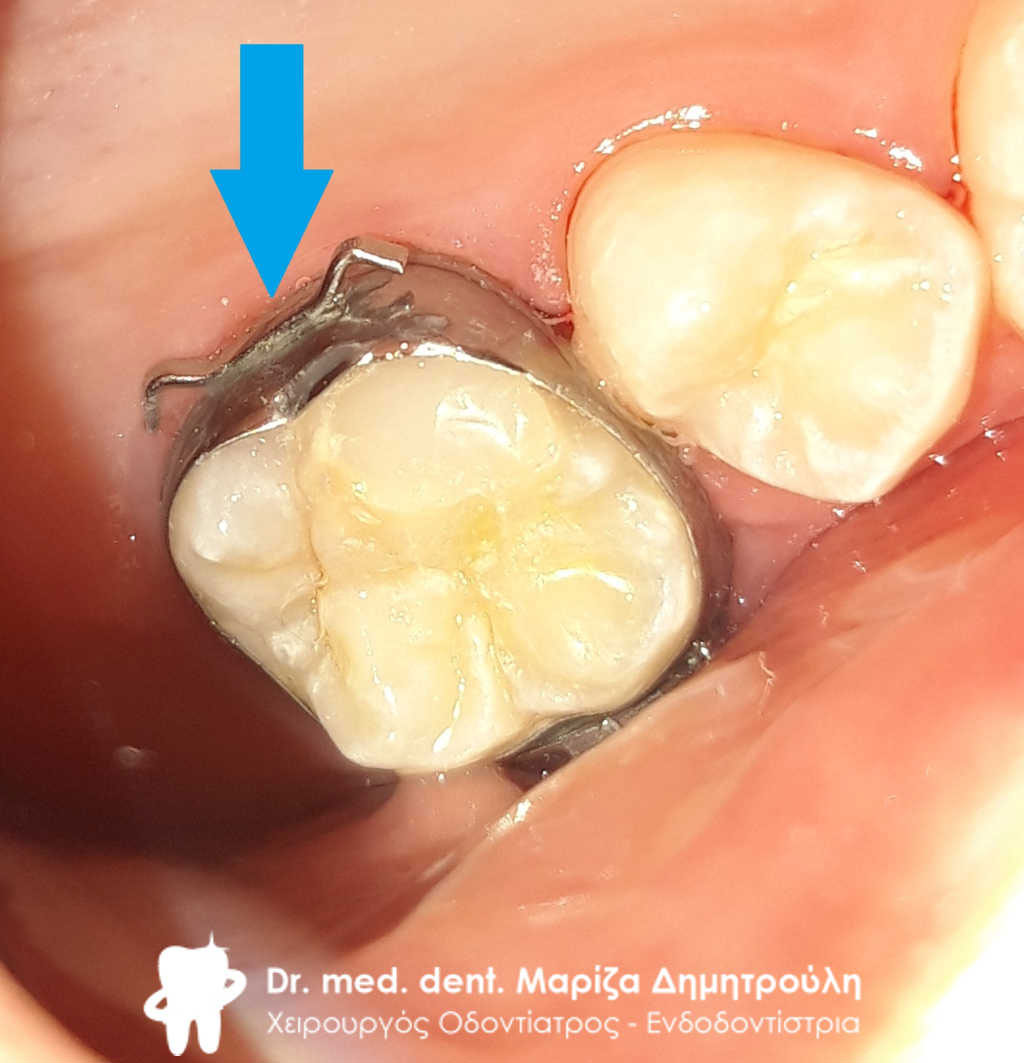

Περιστατικό – Σφράγισμα παιδικού δοντιού

Ο μικρός ασθενής επισκέφτηκε το ιατρείο για την αποκατάσταση του τερηδονισμένου παιδικού δοντιού του. Η ανασύσταση πραγματοποιήθηκε με λευκό σφράγισμα σύνθετης ρητίνης με τη χρήση του απομονωτήρα.

ΠΡΙΝ

Η κοιλότητα του δοντιού καθαρή μετά την αφαίρεση της τερηδόνας

ΜΕΤΑ